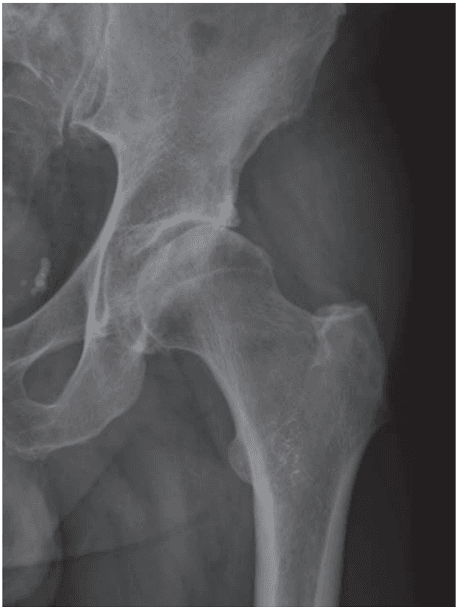

Is intra-articular injection of autologous micro-fragmented adipose tissue effective in hip osteoarthritis? A three year follow-up

Simone Natali, Daniele Screpis, Michele Romeo, Stefano Magnanelli, Giuseppe Rovere, Amarossi Andrea, Lawrence Camarda, Claudio Zorzi, 2022

Adipose-Derived Stem Cells for Hip Osteoarthritis: A Promising Case Series

Vito Coco, Filippo Boriani, Stefano Zaffagnini, Alessandro Russo, Annals of Case Reports & Reviews, 2021

Mesenchymal Stem Cells injection in hip osteoarthritis: preliminary results

Carlo Dall'Oca, Stefano Breda, Nicholas Elena, Roberto Valentini, Elena Manuela Samaila, Bruno Magnan, Acta Biomedica, 2019